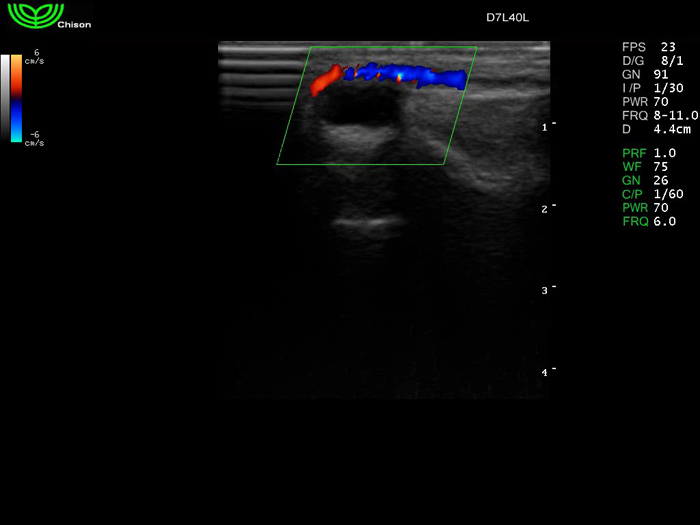

D7L40L 7.5МГц, линейный.

4.0МГц – 13.0 МГц. Применения: грудь, малые органы, нервы, сосуды, венозная катетеризация, мышцы и скелет, управление биопсией. |